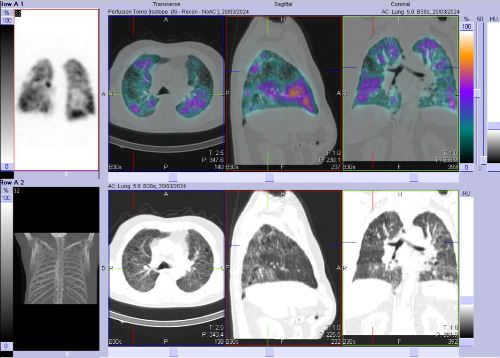

/ Obr. č. 2-7: SPECT/CT plic se zaměřením na vícečetné perfuzní defekty v obou plicních křídlech.

Na scintigramech pozorujeme vícečetné perfuzní defekty v obou plicích (v horním a dolním laloku pravé plíce a v horním a dolním laloku levé plíce). Dále je homogenní distribuce ventilace v obou plicích.

SPECT/CT potvrzuje tyto perfuzní defekty. Na ldCT je dále patrná Vámi popisovaná nespecifická intersticiální pneumonie, taktéž emfyzém, to však nevysvětluje diskrepanci mezi perfuzí a ventilací. Jde tedy o tzv. V/P mismatch.

Závěr: vícečetné perfuzní defekty v obou plicích (v horním a dolním laloku pravé plíce a v horním a dolním laloku levé plíce). Homogenní distribuce ventilace v obou plicích. V/P mismatch.

Nález svědčí pro plicní embolizaci do obou plicních křídel.